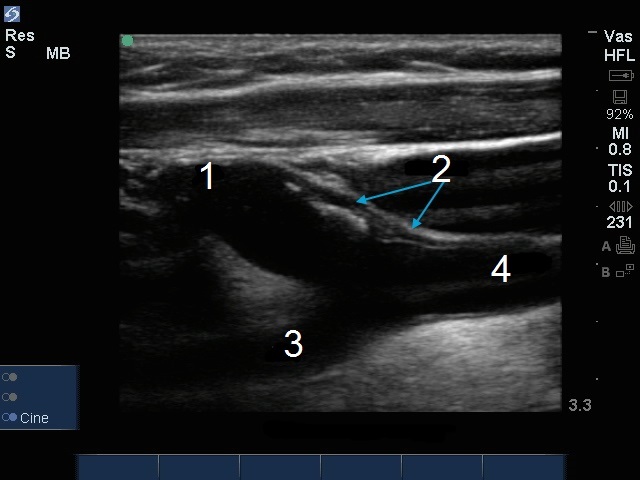

Placa de la arteria carótida interna (ACI)

1. Arteria carótida interna (ACI)

2. Placa

3. Arteria carótida primitiva

4. Arteria carótida externa (ACE)